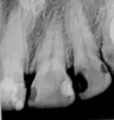

Я нашла у себя кариес на двух передних зубах. И хочу поставить пломбу. Одни мне говорят что если поставить пломбу, то зуб начнет гнить и пломбу будет сильно видно, а другие говорят, что пломбу не отличить от настоящего зуба. Скажите что делать?

Добрый день. Уважаемая Светлана, скорей всего вы не правильно все поняли, так как зуб не может гнить при грамотной установки пломбы, скорее всего, есть какая-та другая причина. Если вы попадете к грамотному терапевту и после снятия кариозных отложений сделаете красивую реставрацию, то все будет отлично и никто не отличит пломбу от своего зуба. Но повторяюсь, вам необходимо обратиться к терапевту с опытом и с навыками не просто установки пломб, а с навыками и умением реставрировать коронковую часть зуба. Всего вам доброго.

P.S Хочу добавить, что реставрация передних зубов очень тонкая и кропотливая работа и требует опыта в изготовлении в полости рта терапевтических виниров (метод реставрации путем перекрытия всей фронтальной части зуба для достижения высокой эстетики).